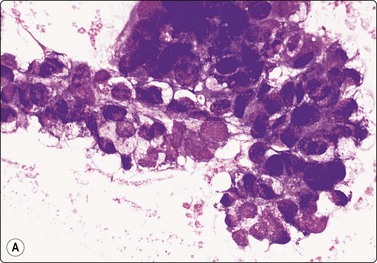

Seminoma (Figs 13.30 and 13.31)14,50,57-63,65,66

image image

Fig. 13.30 Seminoma

(A) Dispersed cells with large pale nuclei and poorly defined cytoplasm; note ‘tigroid’ background, smudged nuclei and small lymphocytes (MGG, HP); (B) Dispersed cells; moderately pleomorphic vesicular nuclei; single or multiple prominent nucleoli; many scattered lymphocytes (Pap, HP).

Criteria for diagnosis

Cell-rich smears,

Dispersed cells, little tendency to clustering,

Highly fragile cytoplasm and nuclei (’tigroid background’ (TB) and nuclear trailing),

Large rounded vesicular nuclei; distinct nucleoli, smaller than in embryonal carcinoma,

Irregular chromatin with some clearing,

Abundant fragile, pale/clear cytoplasm; some marginal vacuoles (punched-out vacuoles),

Lymphocytes, plasma cells,

Tangled chromatin threads (seminoma cells and lymphocytes),

Some epithelioid histiocytes, epithelioid granulomas (variable),

Striking contrast in size between seminoma cells and the background of lymphocytes and plasma cells.

Immunocytochemistry: cells positive for PLAP, c-kit (CD117) and OCT 3/4, and negative for CD30, AE1/AE3, and CK7, CK8, CK18 and CK19, although focal pancytokeratin-positive cells may be seen.

Seminoma is a highly cellular neoplasm of poorly cohesive cells and little stroma. The presence of a lace-like tigroid background (TB), and the high cellularity including lymphocytes account for the intense navy-blue color of the smears. This may suggest the diagnosis even before microscopic study. Comments about the origin of TB and the distinction from ‘lymphoglandular bodies’ have been made elsewhere.60 TB may go unnoticed in Pap-stained smears, but is more conspicuous in DQ smears (Fig. 13.30). A diagnosis of seminoma should not be based solely on the presence of TB or TB-like material. We have observed TB-like material also in aspirates of embryonal carcinoma. The contrary is also true: seminoma should not be ruled out simply because the pathologist is unable to identify TB.14 Large seminomas may show prominent necrosis. Necrosis is a major cause of false negatives in testicular FNA.59 Tumor giant cells or syncytiotrophoblastic cells may be seen in aspirates of seminoma, but can also be found in embryonal carcinoma, mixed TGCT and in trophoblastic tumors.

The plasmatic membrane is well-defined in seminoma, but it is difficult to see in embryonal carcinoma. When lymphocytes, plasma cells, histiocytes and epithelioid granulomas are abundant and seminoma cells scarce, a diagnosis of granulomatous orchitis may be entertained: the absence of spermatozoids and of the germinal line suggest a seminoma.60

Chromatin trailing may be prominent, particularly if the sample was smeared vigorously. This artifact has no diagnostic value in itself, since it may occur also in embryonal carcinoma, yolk sac tumors, lymphomas and acute orchitis. When the smear is dominated by this artifact, and there are no acute inflammatory cells and no spermatogenesis, the pathologist must search carefully for preserved diagnostic cells. In this situation, a tentative diagnosis of seminoma may be made.14

Lymphocytes, plasma cells and even ‘lymphoglandular bodies’ may be prominent in smears of seminoma and may lead to an erroneous diagnosis of lymphoma. Lymphoblasts may also be mistaken for seminoma cells.

Familiarity with the cytology of testicular seminoma helps in the recognition of extragonadal seminoma and metastatic seminomas (Fig. 13.31). Immunostaining may be of help in doubtful cases.69